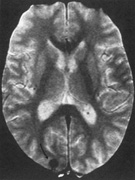

The upper and lower banks can also be involved separately. Ischemia can do this because the banks have separate blood supplies. Upper bank infarcts cause homonymous contralateral inferior quadrantanopia (Fig. 10) and lower bank infarcts cause superior quadrantanopia. Although altitudinal defects have been reported occasionally,47,48 most quadrantic defects do not align at the horizontal meridian, because the upper field merges without interruption into the lower field in the depths of the calcarine fissure. Thus it has been argued that quadrantic defects that respect the horizontal meridian are caused by involvement of area V2, surrounding striate cortex,49 which remains controversial. Quadrantanopias are three times more common with striate lesions than with optic radiation lesions.33 Striate quadrantanopias are more frequently isolated signs but can be associated with other signs of higher cortical visual dysfunction, such as pure alexia or hemiachromatopsia, whereas optic radiation quadrantanopias usually are accompanied by hemiparesis, dysphasia, or amnestic problems.33

Fig. 10. Striate quadrantanopia. A. A 68-year-old woman with a stroke 3 years previously, causing left inferior quadrantanopia. B. MRI shows infarct of the superior bank of the right calcarine cortex.

Selective lesions can also occur along the anterior-posterior extent of striate cortex. A lesion of the occipital pole alone causes homonymous central hemiscotomata (Fig. 11).44,50 This can occur with watershed infarcts during systemic hypoperfusion. Slightly more anterior lesions in the middle zone of striate cortex cause homonymous peripheral scotomata (Fig. 12). The highly congruent, homonymous nature of these defects and their restriction to one hemifield differentiate these from ocular causes of central or paracentral visual loss. Lesions with such small field defects can be missed on CT.43 MRI with coronal sections through the occipital lobes should be performed, although even this may miss small lesions, particularly at the occipital pole.